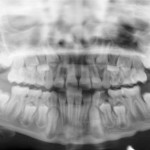

Trattamento combinato parodontale e restaurativo per la riabilitazione del settore anteriore

Il caso clinico descrive un approccio inter-disciplinare di successo per il trattamento dei settori anteriori compromessi dal punto di vista estetico. In una prima...